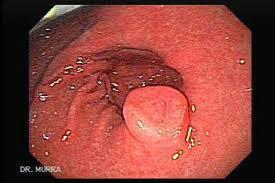

Se manifiesta con disfagia, impactación de los alimentos y sintomatología de reflujo que no remite, además de otros problemas como el dolor al tragar y los vómitos. Actualmente, el tratamiento estándar para esta enfermedad en pediatría consiste en la administración de corticoides deglutidos, además de que recientemente se han empezado a probar estrategias basadas en anticuerpos monoclonales, pero los expertos consideran necesario abrir nuevas vías para mejorar el abordaje de estos pacientes en los próximos años. Una de las cosas que más preocupan actualmente a los investigadores en este campo es que algunos pacientes reaccionan mejor a las terapias, mientras que otros se comportan de manera diferente, lo que pone de relieve la importancia de estudiar más a fondo la etiopatogenia y conocer mejor los aspectos genéticos de la enfermedad. La Unidad de Gastroenterología, Hepatología y Nutrición Pediátrica del Hospital Valle de Hebrón, de Barcelona, ha anunciado que en los próximos meses dará inicio en este centro un ensayo clínico innovador con beclometasona dipropionato, un corticoide que se utiliza para la prevención y el tratamiento de las crisis de asma. Los resultados de diversos estudios experimentales que constan en la literatura científica apuntan a que posiblemente se trata del corticoide que ofrece un mayor efecto para bloquear los receptores de IgE específicos del esófago, por lo que se espera que ofrezca beneficios clínicos para los pacientes con esta enfermedad.Revista Salud y Bienestar